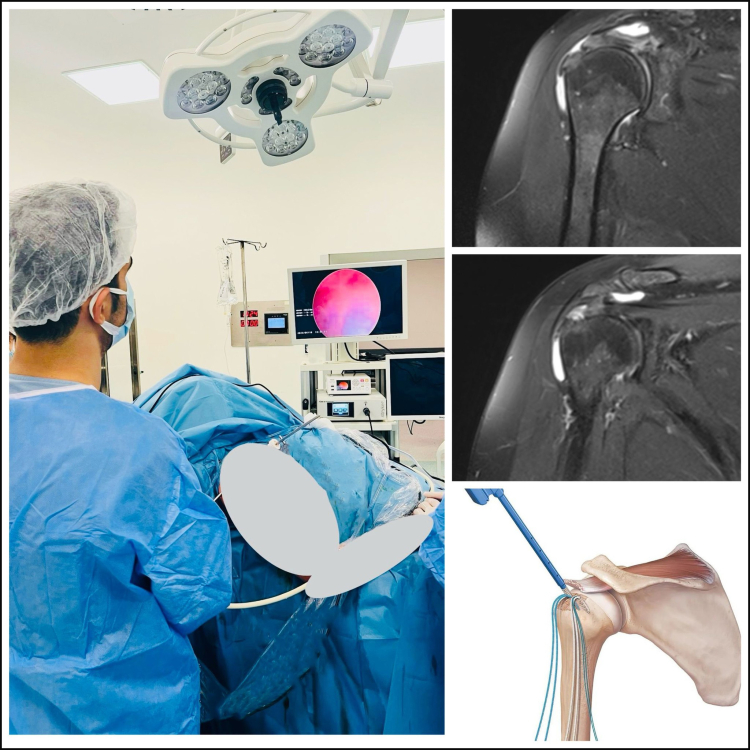

Yalova Eğitim ve Araştırma Hastanesi’nde artık, Başhekim Yardımcısı ve Ortopedi & Travmatoloji Uzmanı Op.Dr. Seçkin ÖZCAN tarafından tamamen kapalı teknikler kullanılarak Yalova genelinde ilk defa yapılmaya başlanan artroskopik Rotator Cuff onarım ameliyatları gerçekleştirilebiliyor. 51 yaşındaki D.B, uzun zamandır sağ omuzunda ağrı, hareket kısıtlığı ve geceleri ağrı nedeniyle uyuyamama şikayetleri ile Yalova Eğitim ve Araştırma Hastanesi’ne başvurdu. Yapılan tetkiklerde omuz liflerinde kopma olduğu tespit edildi. Uygulanan medikal tedaviye rağmen şikâyetleri geçmeyen D.B için operasyon kararı alındı. Başhekim Yardımcısı Ortopedi ve Travmatoloji Uzmanı Op. Dr. Seçkin ÖZCAN tarafından tamamen kapalı (Omuz Artroskopik) omuz ameliyatı gerçekleştirildi.

Yalova Eğiti ve Araştırma Hastanesi, başarılı geçen operasyon sonrasında hastaya geçmiş olsun dileklerini iletirken aynı zamanda da hastalık hakkında detaylı bir bilgi paylaşımında bulundu. Hastane tarafından yapılan paylaşımda, ‘’Rotator Cuff Sendromu, omuz ekleminde yer alan ve hareketi sağlayan tendonların zedelenmesi veya yırtılması sonucu ortaya çıkan bir yaralanmadır. Omuzda ağrıya, hareket kısıtlılığına ve güçsüzlüğe neden olan Rotator Cuff Sendromunun iki temel nedeni yaralanma ve tendonlardaki yaşa bağlı yıpranmadır. Tedavi seçenekleri arasında istirahat, ağrı kesici ilaçlar ve fizik tedavi uygulamaları yer almaktadır. Gerektiğinde ise cerrahi tedavi uygulanmaktadır. Cerrahi tedavide ise günümüzde önerilen yöntem artroskopik yöntemle tamamen kapalı olarak yırtık olan kasların tamir işlemidir. Kapalı omuz ameliyatlarının iyileşme süreci açık ameliyatlara göre daha hızlı olup ameliyat sonrasındaki süreç hastalarımız için daha konforludur’’ ifadelerine yer verildi.